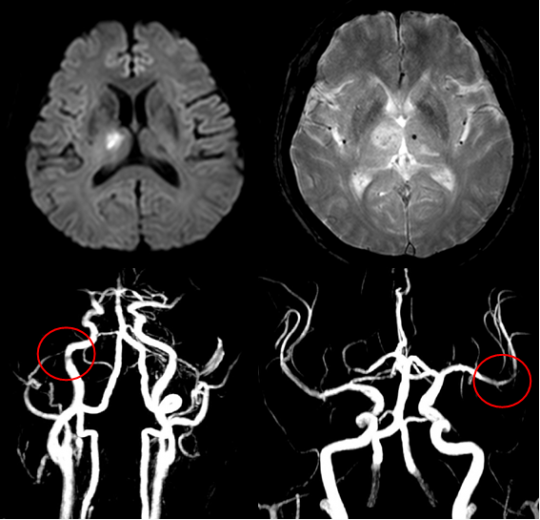

이 질병을 진단하는 검사로는 몇 가지가 이어질 수 있답니다. 뇌졸중에는 뇌출혈과 뇌경색이 있는데, 이 양쪽 모두는 양상이 다르며 무엇이냐에 따라서 치료 절차도 상이하기 때문에 뇌경색 검사방법으로 진단을 정확하게 받는 것이 선행되어야 하고 중요한 부분이라고 할 수 있어요. 우선 뇌경색 초기증상이 보인다면 방문을 하여서 전문가와 상담을 진행하게 되겠고, 진행되는 뇌경색 검사방법으로는 뇌혈관 자기 공명영상, 공명영상 촬영술, 전산화 단층 촬영, 심장 초음파, 경동맥 초음파, 뇌혈관 초음파 등의 방식으로 환자의 현재 상태를 파악하여 치료가 진행되겠죠.